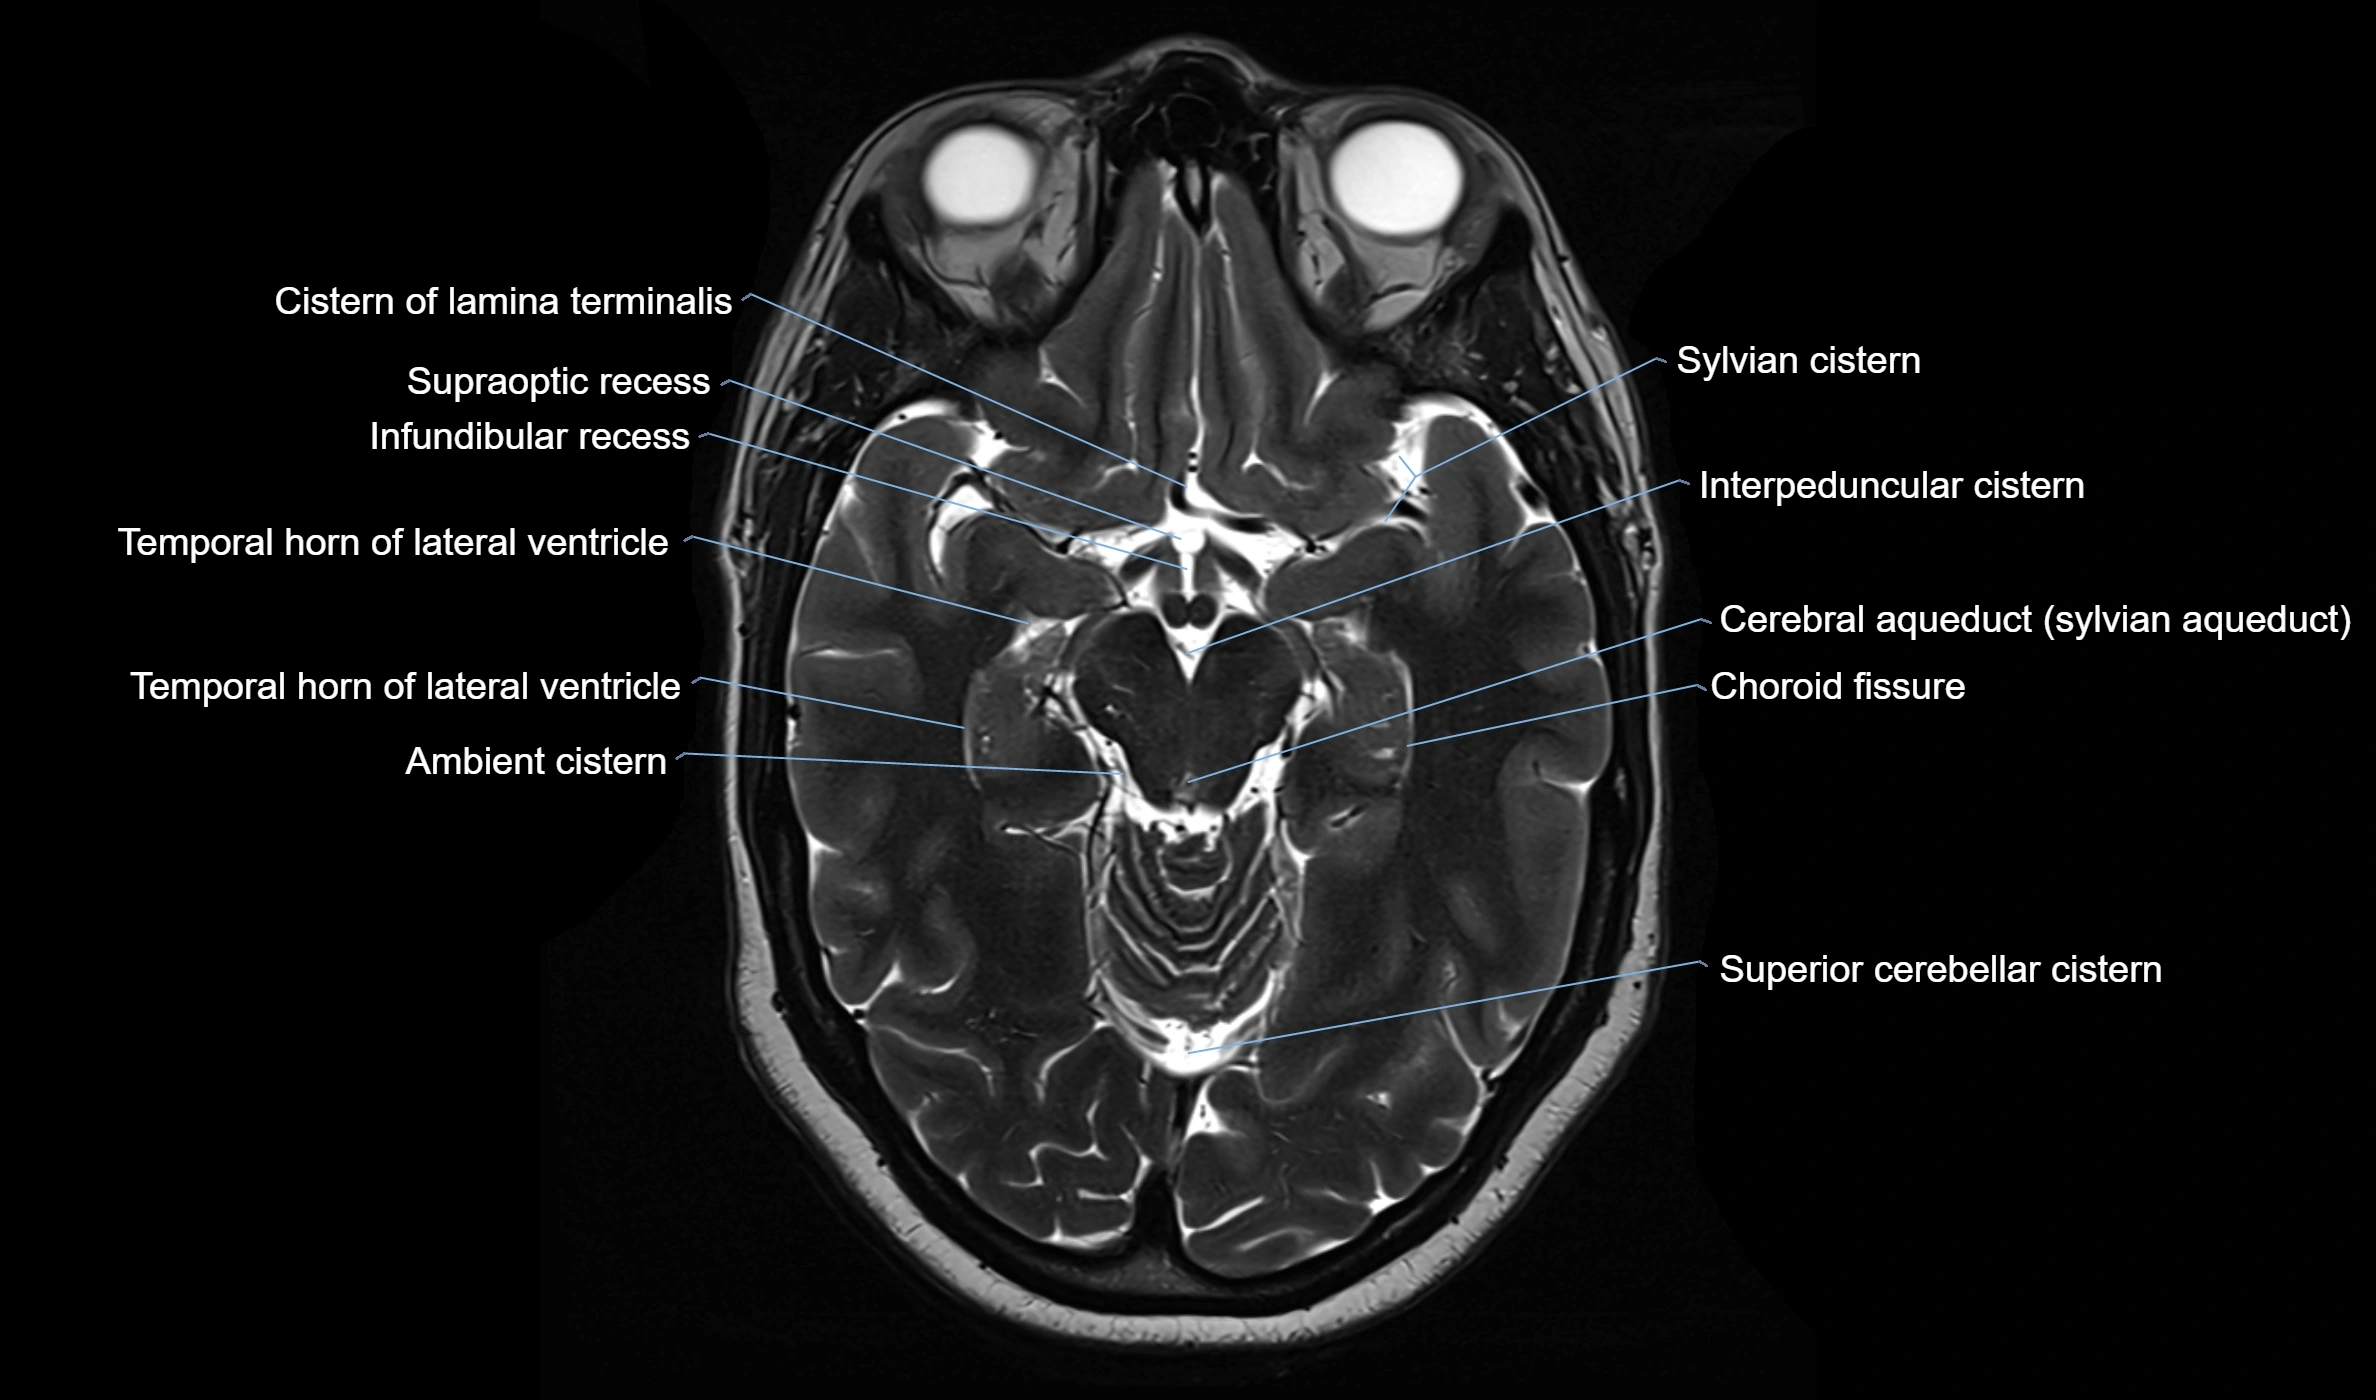

Ambient cistern

The ambient cistern is a paired, narrow, and elongated subarachnoid space located bilaterally along the lateral aspect of the midbrain. It serves as a conduit between the interpeduncular cistern anteriorly and the quadrigeminal cistern posteriorly. This cistern houses critical neurovascular structures, including parts of the posterior cerebral artery, superior cerebellar artery, trochlear nerve (cranial nerve IV), and the basal vein of Rosenthal. It plays an important role in the circulation of cerebrospinal fluid (CSF) and provides an anatomical corridor for various vessels and nerves passing around the midbrain.

MRI images

image